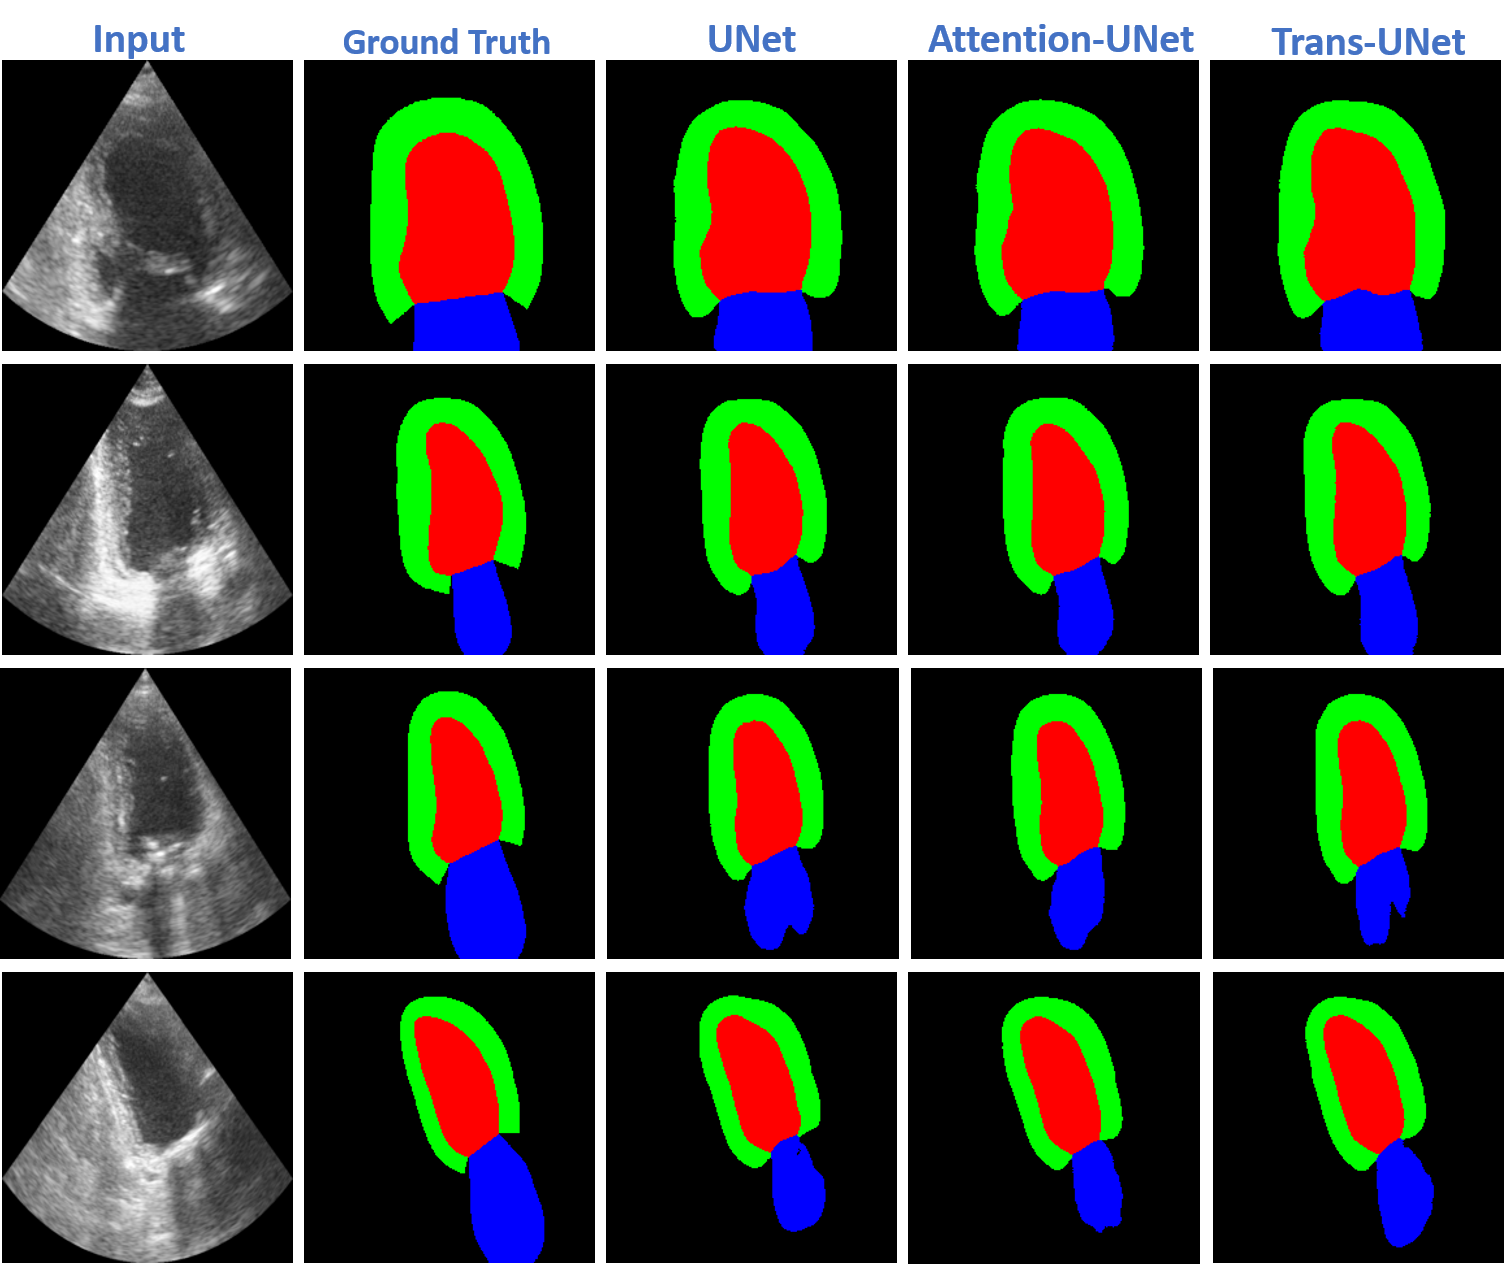

To address these gaps, this study performs a comprehensive, controlled comparison of U-Net, Attention U-Net, and TransUNet on the CAMUS dataset using identical preprocessing, data splits, loss functions, and evaluation metrics. The experiments also assess the effect of data representation (NIfTI vs. PNG-16bit) and self-supervised pretraining (SSL) on model performance and generalization. This unified analysis provides clear insights into the trade-offs among architectures and establishes reproducible baselines for future echocardiographic segmentation research (see Fig. 2).

Refer to caption

Figure 2: Unified workflow for cardiac ultrasound segmentation combining literature review, strict preprocessing, model training, and evaluation. The left block summarizes the survey of cardiac imaging literature and datasets (including CAMUS and ACDC). The preprocessing stage applies PNG-16-bit conversion, strict manifest pairing, normalization, and quality checks. The modeling stage integrates U-Net, Attention U-Net, and TransUNet architectures, supported by SimCLR pretraining and SAM-based pseudo-labeling to improve encoder initialization and make use of unlabeled frames. The evaluation module compares model performance across architectures, quantifies gains from SSL, and highlights improvements in segmentation accuracy and anatomical consistency. The workflow emphasizes how preprocessing fidelity, SAM, and SSL improve reproducibility and strengthen downstream segmentation outcomes.